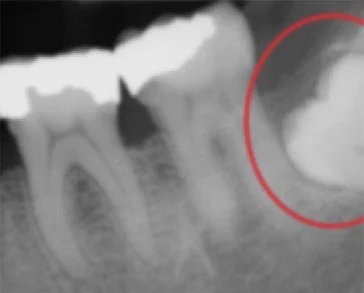

This periapical x-ray shows the top of a molar unable to reach the surface (impacted).